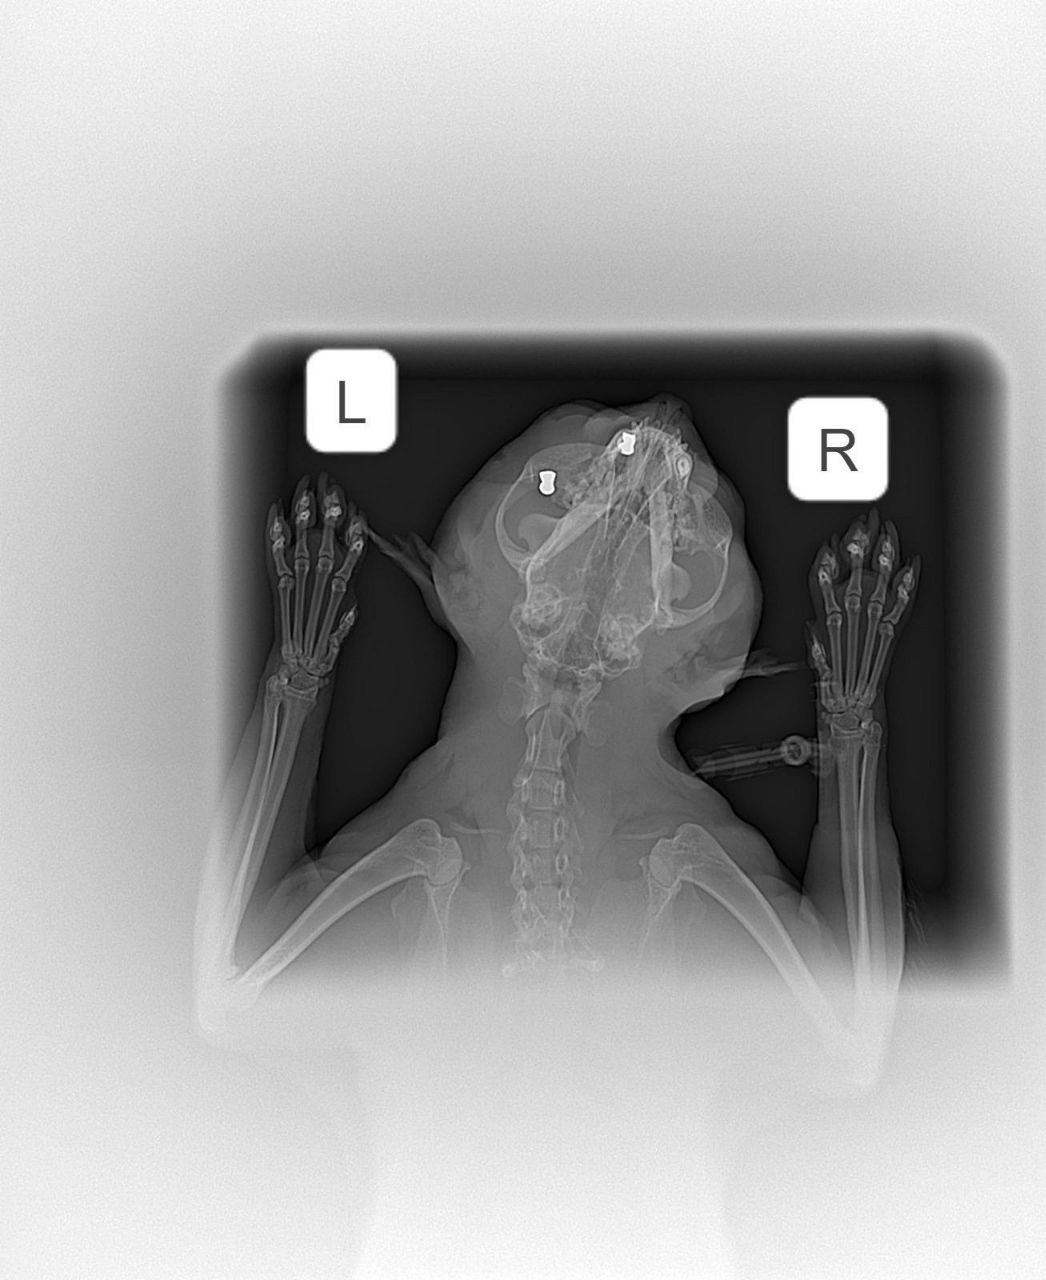

В Арзамасе неизвестный расстрелял кота из «воздушки». Кот ушёл гулять, а вернулся со множеством пуль по всему телу.

Ветеринар заключил, что пушистика привязали, чтобы он не убегал, и стреляли в него. Бедняга сейчас в больнице в тяжёлом состоянии.